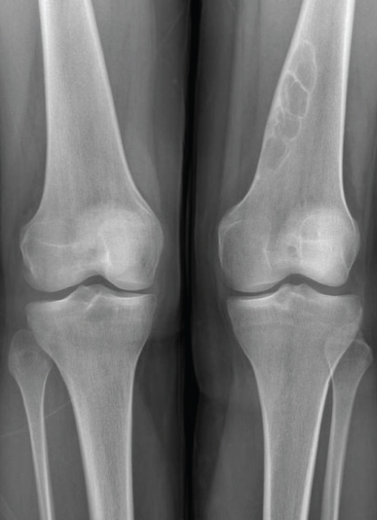

Bow Legs and Knock Knees

Angular and Rotational Deformities